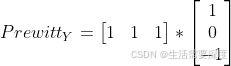

效果